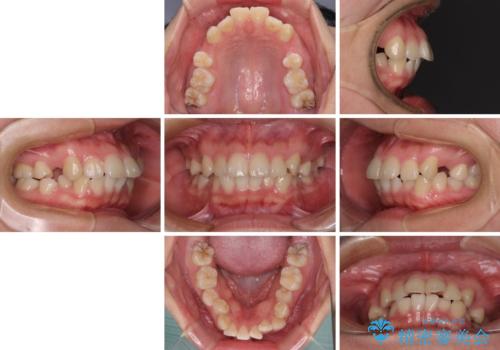

- 口元の閉じにくさを気にして来院された患者様です。

地元で矯正治療を始める予定で上顎左右第1小臼歯2本を抜歯したものの、その後転居したため治療が滞っているとのことでした。

上下ともに歯列が前方に突出していたため、上下左右の第一小臼歯4本を抜去する方針(既に上顎は抜歯されています)で、ワイヤー装置による矯正治療を行うこととしました。

舌の突出癖による影響もあったため、舌のトレーニングを並行して実施しました。